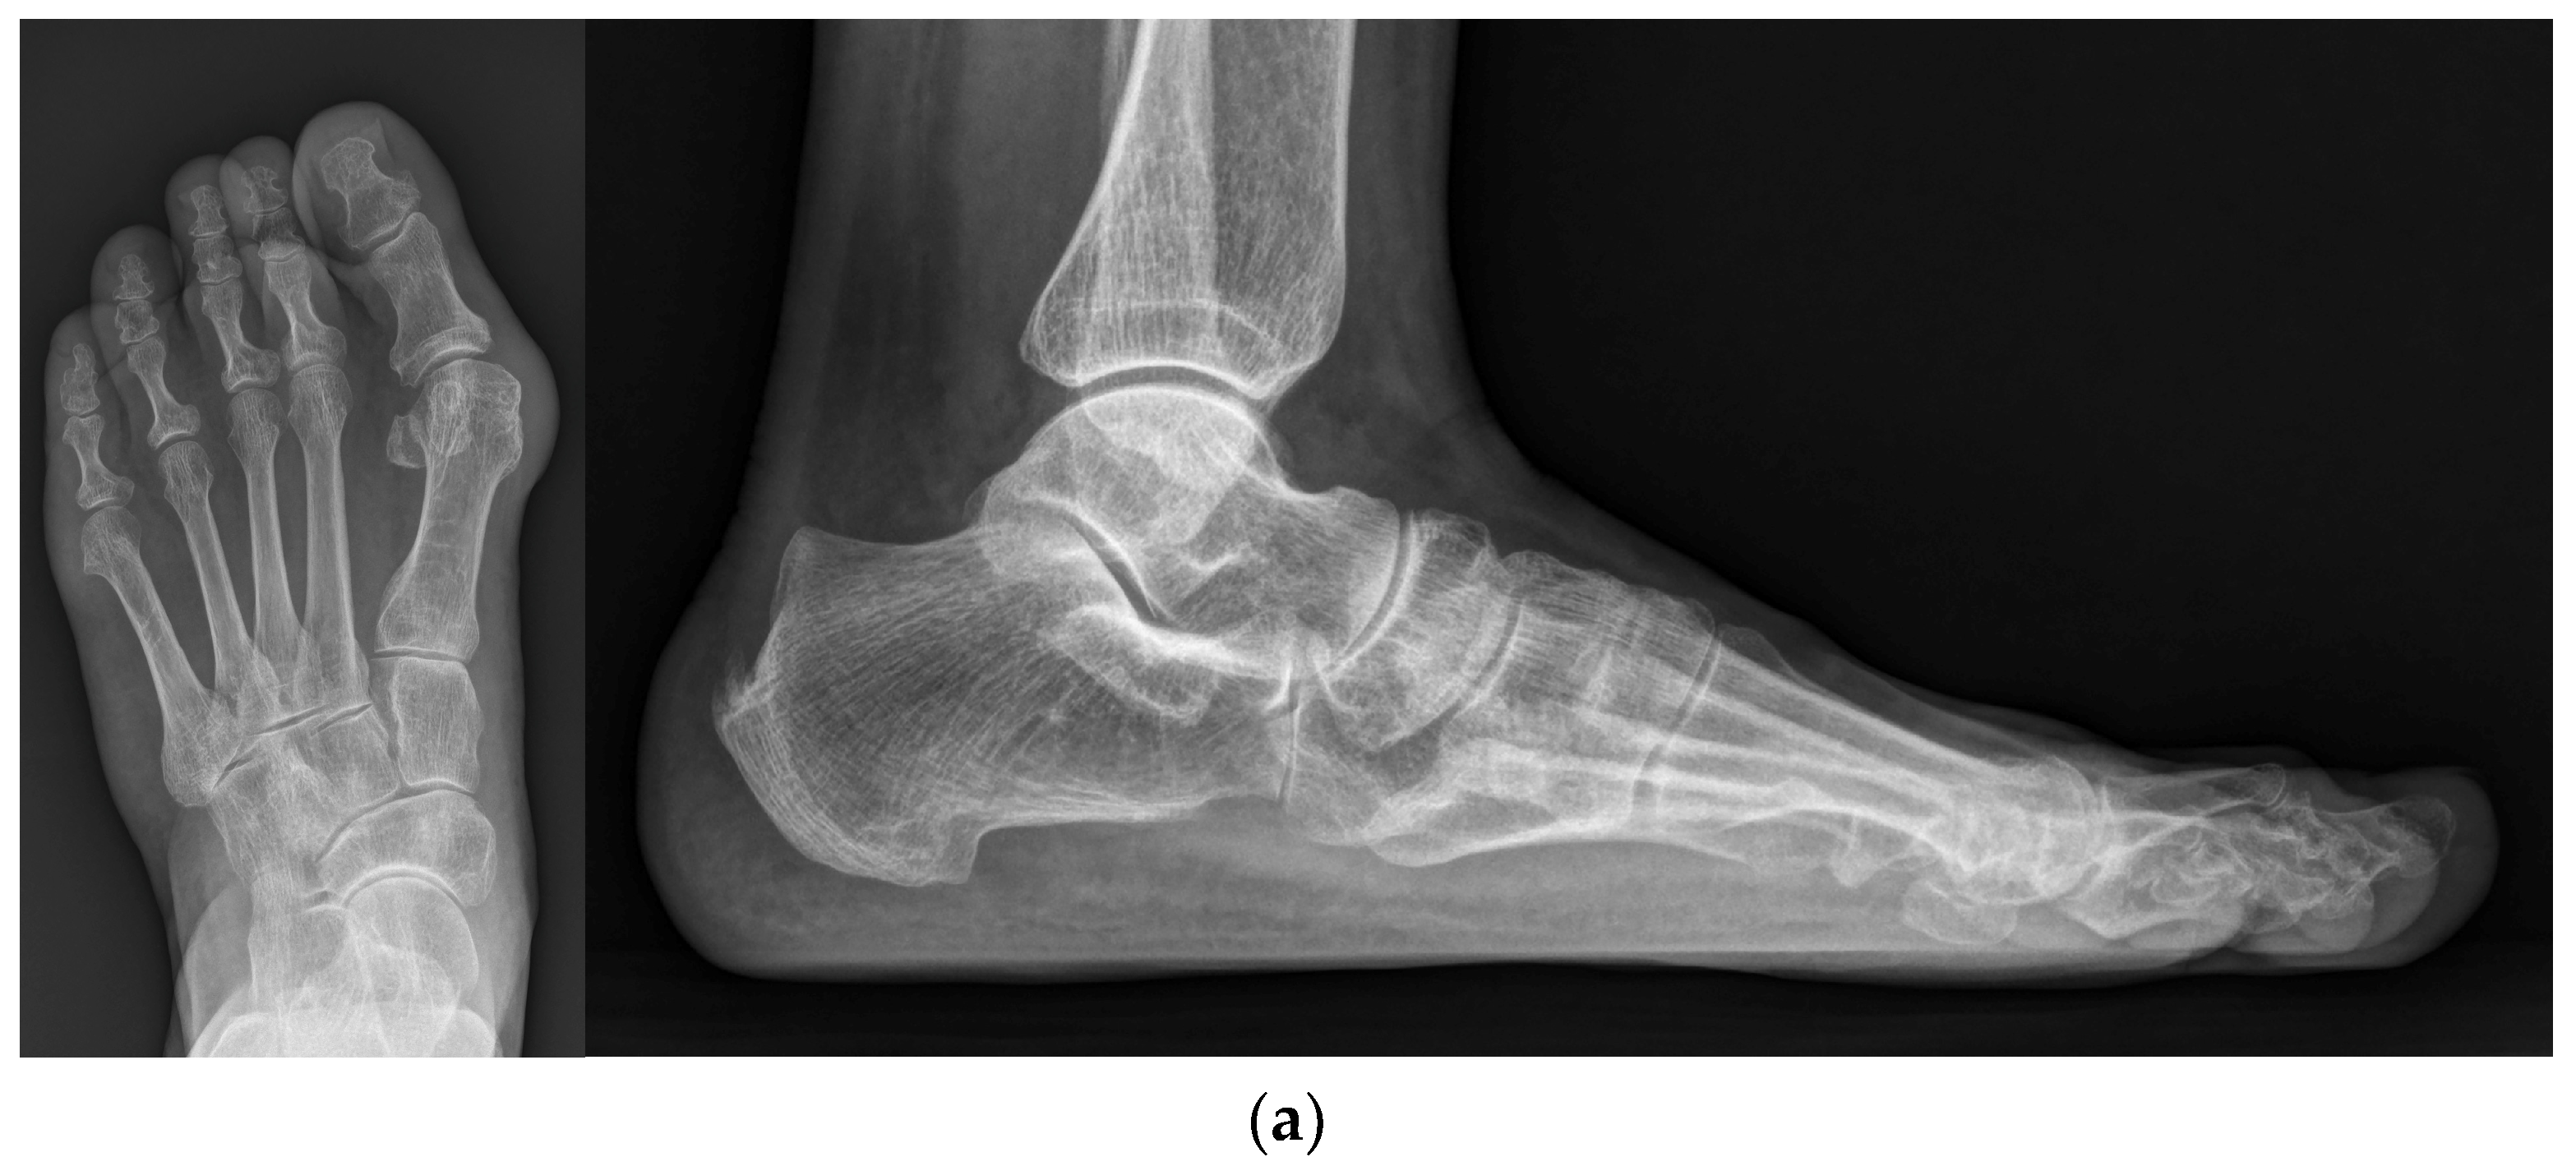

Figure 3.

(a) Preoperative standing foot anteroposterior and lateral radiographs; (b) Intraoperative foot anteroposterior and lateral fluoroscopy images; (c) Standing foot anteroposterior and lateral radiographs at 2 months post operation; (d) Standing foot anteroposterior and lateral radiographs at the final follow-up.